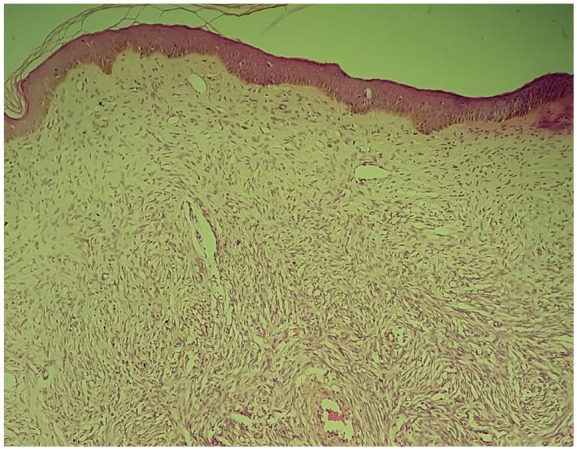

Dermatofibrosarcoma protuberans (DFSP) is an extremely rare cutaneous tumor in children, marked by local aggressiveness, slow growth, high recurrence rate, and low metastatic potential. Its prevalence is often underestimated in children due to its slow growth and frequent misdiagnosis. Diagnosing DFSP can be challenging due to nonspecific symptoms. While most cases present as nodular lesions on the trunk or proximal extremities, some lesions, such as atrophic plaques or sclerotic nodular plaques, can mimic vascular malformations and confuse clinicians. Histologic and immunohistochemical studies are essential for definitive diagnosis. The treatment of choice is complete surgical resection with wide margins to reduce the risk of recurrence. We report two pediatric DFSP cases on the trunk, including one mimicking vascular malformations. Both cases had successful 4 cm margin resections, with no recurrences observed after 6 months and 2 years of follow-up, respectively. Continuous surveillance will be maintained for at least 5 years.